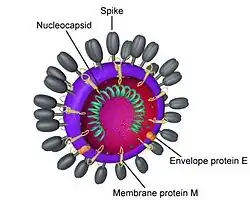

Baker has also worked closely with coronaviruses, the causative agent of severe acute respiratory syndrome. These are viruses that affect mostly the upper respiratory and GI tract of humans and are named because of their crown-like appearance under the electron microscope. Currently her lab is using a mouse model to test the function and inhibition of certain proteases involved in coronavirus infection.[6]